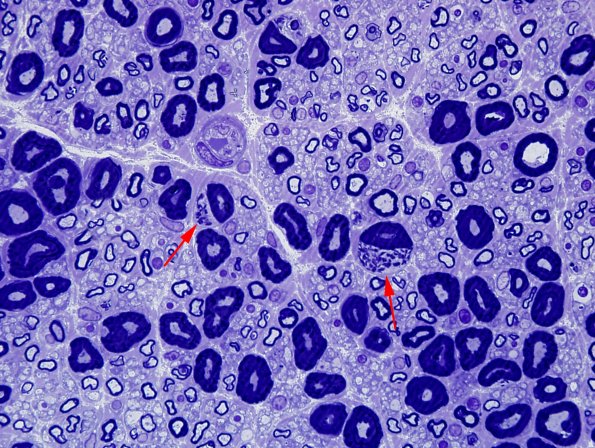

Several Schwann cells of large myelinated axons contain multiple Pi granules. (One micron thick toluidine blue stained plastic embedded section)